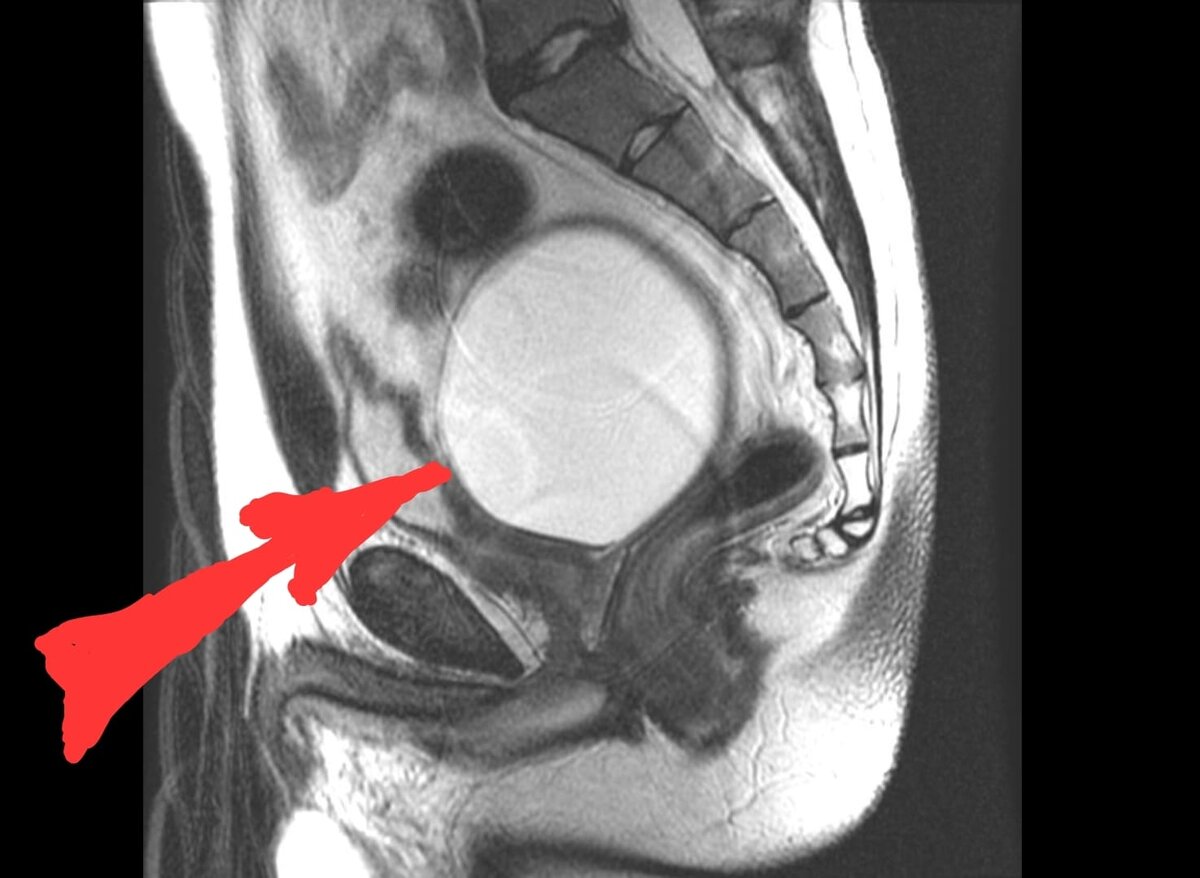

Женщина оказалась адекватной и уже на следующий день сделала МРТ. Звонит в слезах. На МРТ обнаружилась киста в малом тазу. Кисты дело не редкое у женщин и страшного в них ничего нет. Они могут немотивированно как возникать, так и проходить бесследно. Очень часто, киста проходит сама по себе после родов. Но в этом случае, всё оказалось серьёзнее. Кисточка имеет размер 8 см в диаметре! Да она одну треть объёма малого таза занимает. И не факт, что она дальше не растёт. А чревато это снижением кровоснабжения яичника, матки, что в свою очередь может привезти и к бесплодию, что ещё хуже к онкологии. На данном этапе всё это, пока, зашло не далеко и дальнейшее обследование даст ответ, что с ней делать, но поясничные боли вполне могли быть спровоцированы этой кистой. Да дело, даже не в этом. Этот псевдо остеопат поставил человека на грань более серьёзных заболеваний, которые могли бы сделать её инвалидом. Не известно сколько долго изменения накапливались и в итоге привели бы к необратимым последствиям. Так бы он её и дальше лечил, беря не малые деньги ни за что.

Та самая киста в области малого таза.